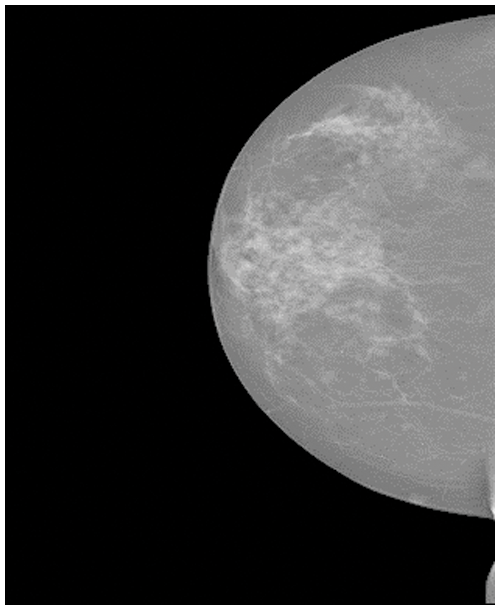

The image of breast cancer is shown in Fig. 1. Invasive carcinoma and carcinoma in situ are two types of breast cancer [19]. Carcinoma in situ cannot be upgraded in the body. About one-third of new breast cancer is carcinoma in situ [20]. Most newly diagnosed breast cancer is invasive. Invasive cancer begins in the mammary duct and can spread to other breast sites [21].

Figure 1: The breast cancer image [22]